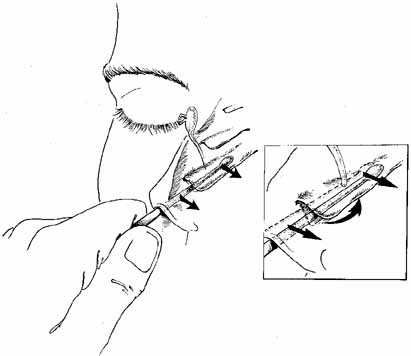

is aided by irrigation with 0.5 mL of an antibiotic steroid solution.  Fig. 19 Probing and irrigation of the nasolacrimal system. Hydraulic pressure is

used in an attempt to force fluid through the obstruction at the valve

of Hasner. If this attempt is unsuccessful, the cannula is slipped

down to the point of obstruction and pushed through gently but firmly. Dye

is injected from the syringe, and the patency of the system is confirmed

by suctioning the dye from the inferior meatus with a soft pediatric-size

plastic suction catheter. Fig. 19 Probing and irrigation of the nasolacrimal system. Hydraulic pressure is

used in an attempt to force fluid through the obstruction at the valve

of Hasner. If this attempt is unsuccessful, the cannula is slipped

down to the point of obstruction and pushed through gently but firmly. Dye

is injected from the syringe, and the patency of the system is confirmed

by suctioning the dye from the inferior meatus with a soft pediatric-size

plastic suction catheter.